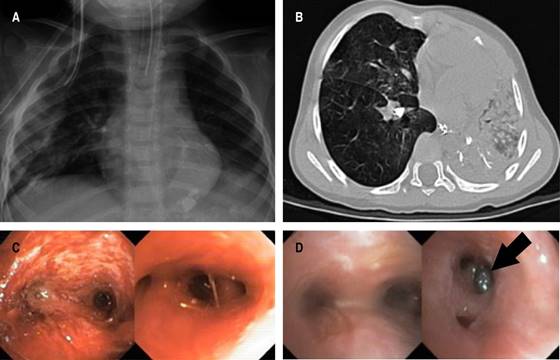

El paciente presentó síndrome de distrés respiratorio agudo pediátrico severo (PARDS) que requirió ventilación convencional durante 20 días, el destete de oxígeno se realizó hasta alcanzar saturaciones normales, fue tratado con doble esquema de antibióticos, esteroide sistémico, micronebulizaciones con esteroide y broncodilatador. Se realizaron tres v ideobroncoscopias flexibles terapéuticas: la primera se efectuó a su ingreso y se observó material inorgánico sólido abundante en la vía aérea, se realizó aspiración y remoción del material referido; en la segunda se observaron datos de traqueoendobronquitis severa, supuración broncopulmonar y zona de isquemia subglótico traqueal, se aspiró material inorgánico sólido; en la tercera broncoscopia se logró la extracción del resto de material sólido (Figura 1).

Figura 1: A) Radiografía anteroposterior. Engrosamiento peribronquial de predominio central, ocupación alveolar difusa bilateral, atelectasia basal derecha, estatus de intubación orotraqueal. B) Intubación selectiva del bronquio derecho con colapso pulmonar y elevación secundaria del hemidiafragma en el lado izquierdo. Engrosamiento de las paredes bronquiales, así como imágenes hiperdensas sugestivas de calcificaciones en pared y luz de los trayectos bronquiales segmentarios en forma bilateral y subsegmentarios en el lóbulo inferior izquierdo. C) Broncoscopia flexible. Se observa edema e hiperemia de la mucosa endobronquial moderada con zonas de isquemia sobre la pared anterior de la tráquea precarinal y supuración broncopulmonar bilateral, restos de contenido inorgánico (arena) sobre carina para el lóbulo basal derecho. D) Broncoscopia flexible. Se observa mucosa endobronquial con edema e hiperemia leve con presencia de cuerpo extraño (piedra) que ocluye la entrada del segmento seis derecho.